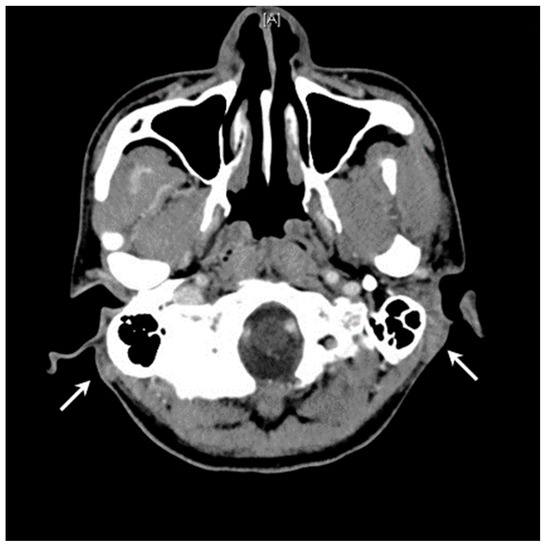

2.1. Case 1

2.2. Case 2

| Head and neck predominance | Strong (80%) [4,7,12] | Slight (54%) [10,12,18,21] | Postauricular region | Postauricular region |